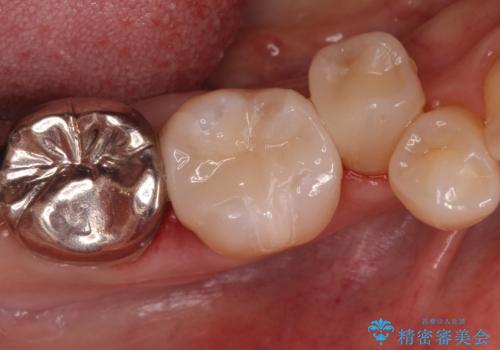

奥歯が欠けた セラミックインレーでの修復後、ナイトガード装着